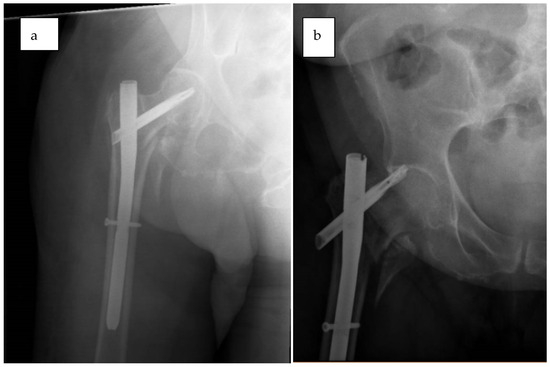

2.7.2. Case 2—Unable to Unleash Traction